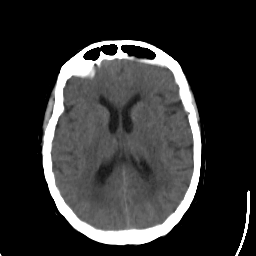

Stroke CT #1 -- Slice #14

[Home][Help][Clinical] Slice 14